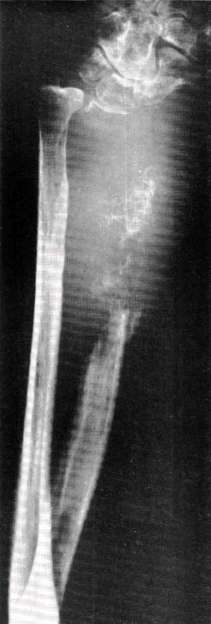

3. L.D. is a 57-year-old male who underwent a right below-elbow amputation in December 1967 because of extensive metastases to the right radius from a hypernephroma (Fig. 3). The operation was performed by conventional methods and a temporary prosthesis, with harness and controls, was applied immediately after surgery. Convalescence was uneventful and the patient was discharged 22 days after surgery, at which time he was capable of controlling the elbow and terminal device in a relatively satisfactory manner. He was fitted with a permanent prosthesis 60 days after the surgical procedure.

Fig. 3. Metastatic lesion of right radius resulting from hypernephroma.